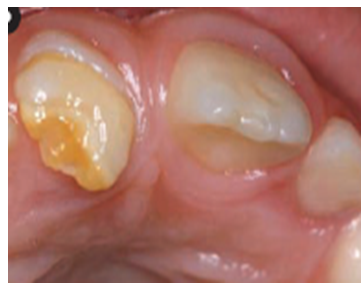

Faktori koji dovode do stvarnja gleđi slabijeg kvaliteta mogu da deluju sistemski, što znači da se radi o promenama u kompletnom organizmu zbog nekih trovanja(npr višak fluora, olovo, neki antibiotici ili drugi lekovi, poremećaji u metabolizmu), opštih oboljenja(virusne i bakterijske infekcije, poremećaji krvi, žutica i sl.) ili pak nedostatka sastojaka ishrane važnih za razvoj mineralizovanih tkiva(vitamin D, kalcijum i sl.). Dejstvo sistemskih faktora se ispoljava na više zuba i to na onim delovima zuba koji su se razvijali u periodu njihovog dejstva, pošto se svi zubi i njihovi delovi ne razvijaju istovremeno. Ostali delovi zuba, ako je faktor delovao samo u određenom vremenskom periodu, ostaju zdravi. Na osnovu položaja oštećenja može da se oderedi kada se i atak dogodio. Za razliku od ovih sistemskih razvojnih poremećaja, nasledni(genetski) poremećaji ne pokazuju specifičnu lokalizaciju veznu za određeni period razvoja zuba, već su nepravilno raspoređni po celoj površini krunice i najšeće na svim zubima.(slika 2.)

Nasledni defekt razvoja gleđi koja je veoma meka i praktično odvojena od površine zuba